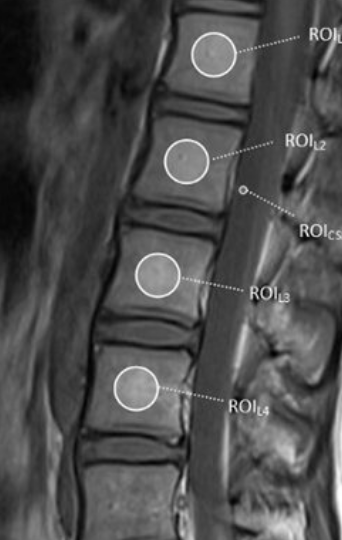

Image Type Lumbar Spine X-Ray CT Scan MRI Scan Anteroposterior (AP) Canal Diameter Cauda Equina Nerve Root Area Conus Medullaris Level Cross-Sectional Area (CSA) of Spinal Canal Disc-Height Index (DHI) Disc Herniation Size Disc Herniation Types Dural Sac CSA Epidural Fat Thickness Filum Terminale Thickness Foraminal Height and Width High-intensity Zone (HIZ) Lateral Recess Width/Depth Modic Endplate Changes (Type I, II, III) Modic (Marrow Signal) Changes Pfirrmann Classification (I-V) Vertebral Bone Quality (VBQ) Score Vertebral Endplate Defects